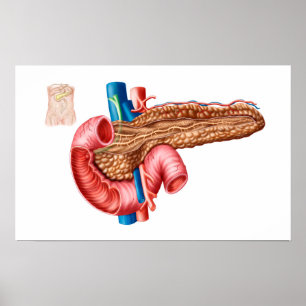

Carta do poster da anatomia do órgão interno do

Preço56,50 €

Impressão humano da anatomia dos órgãos interno

Preço15,60 €